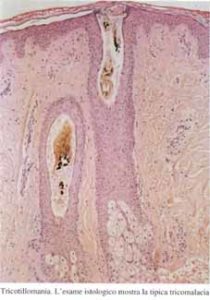

Immagine istopatologica di Tricotillomania